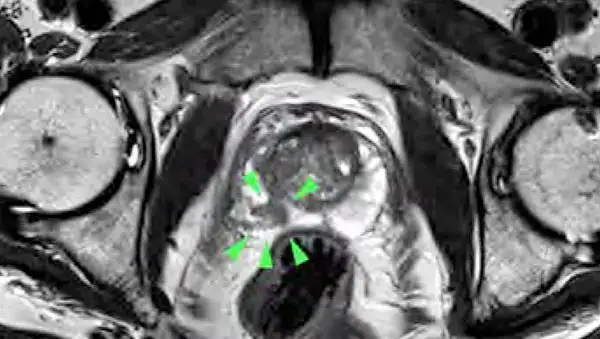

Dr. Dick: Die bisherige Diagnostik weist Lücken auf: So kann der PSA-Wert auch bei nicht-bösartigen Prostata-Vergrößerungen erhöht sein. Und die Abtastung der Prostata ist weder angenehm noch genau. Beim transrektalen Ultraschall über den Mastdarm werden Tumore häufig nicht erfasst und auch die sonographisch gesteuerte Biopsie weist diagnostische Schwächen auf. Deshalb hat die urologische Gesellschaft die multiparametrische Magnetresonanztomografie (mpMRT) in die Leitlinie mit aufgenommen. Diese MRT-Methode ist genau und schonender für den Patienten, auch muss ihm bei 3 Tesla- Geräten keine Spule mehr in den Enddarm eingeführt werden. Neben der Messung anatomischer Werte werden bei diesem speziellen MRT auch die Zelldichte gemessen und die Gewebedurchblutung nach der Gabe von Kontrastmitteln durchgeführt, wodurch wir eine sehr gute Diagnostik haben. Die Datensätze können dann mit den Ergebnissen der Ultraschalluntersuchung verglichen werden. Anschließend kann – wenn nötig – eine gezielte Gewebeprobe entnommen werden.

Mit dem Hochfeld MRT mit 3 Tesla von Siemens steht der Radiologie Darmstadt die neueste Technik – ein hochmodernes Gerät für die mpMRT zur Verfügung – nicht-invasiv und treffsicherer als die ungesteuerte Biopsie. Durch die Kombination räumlich hochauflösender Bilder mit Zelldichtemessungen können wir selbst kleinste Tumore unter 1 cm zuverlässig detektieren. Außerdem können wir entscheiden, ob es sich um einen gutoder bösartigen Tumor oder um eine Entzündung handelt. Die Datensätze können dann mit den Ergebnissen der Ultraschalluntersuchung verglichen und gezielt die richtige weitere Vorgehensweise geplant werden. Neben dem hochmodernen MRT-Gerät verfügen wir als einziger Standort in Südhessen über eine spezielle Software zur Auswertung nach neuesten Richtlinien. Die Auswertung der Daten stellt besondere Anforderungen an den Befunder. Als Praxis sind wir über den BDR (Bund Deutscher Radiologen) zertifiziert, und persönlich bin ich von der Arbeitsgemeinschaft Uroradiologie der Deutschen Röntgengesellschaft mit der Qualitätsstufe Q1 für die mpMRT zertifiziert.